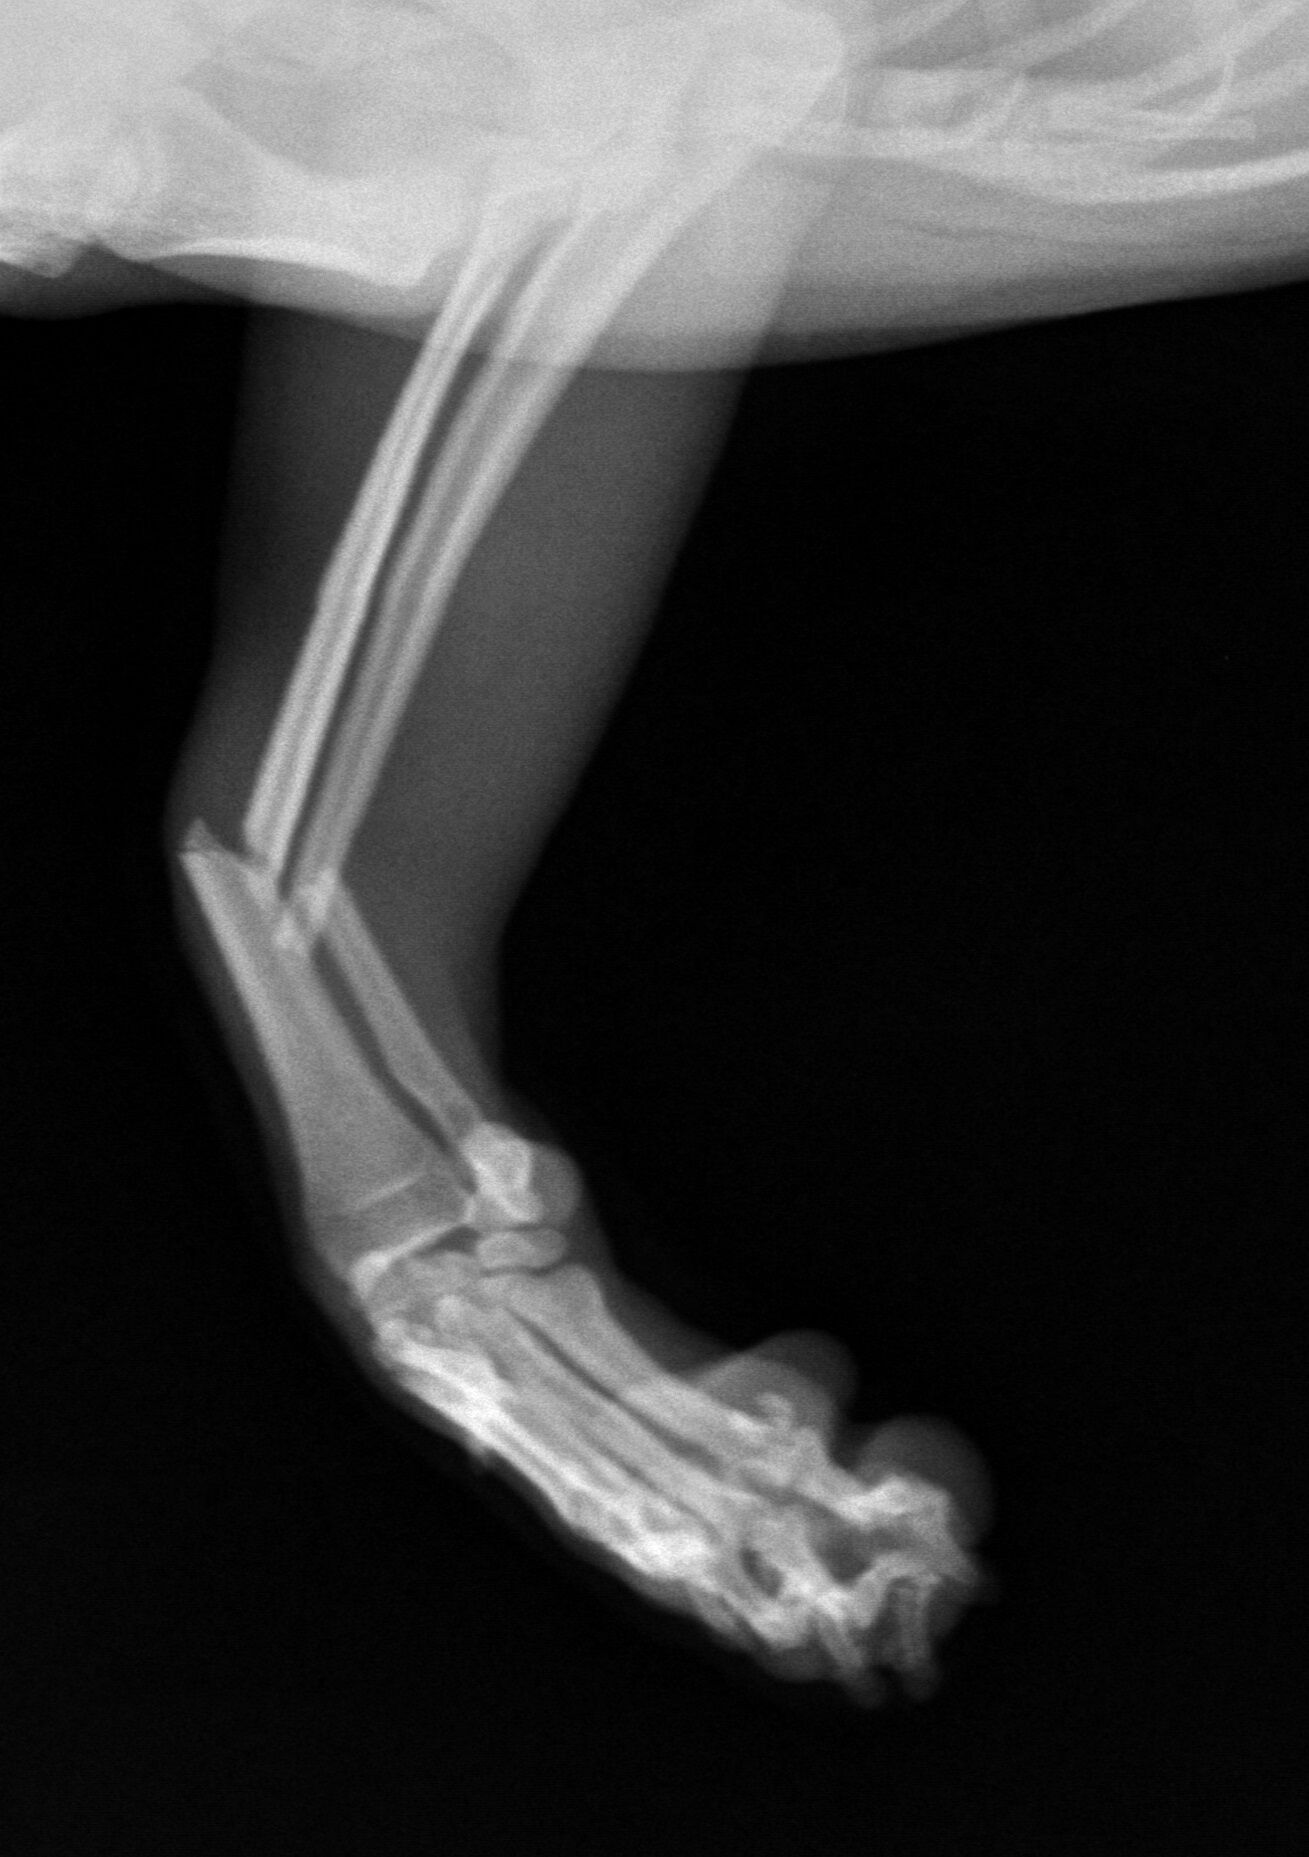

今回は1歳の柴犬の骨折治療です。お子さんが抱っこしていて降ろす際に

着地に失敗して右橈尺骨を骨折してしまいました。